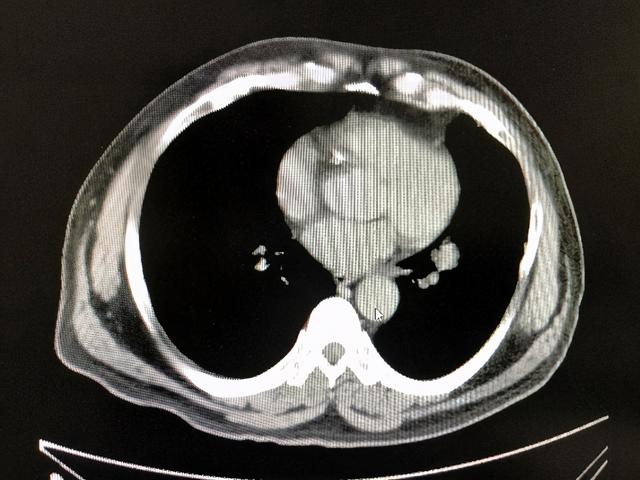

50岁的大爷,因咳嗽、咳痰就诊于南昌市第三医院, 查胸部CT:发现左下肺肿物,伴4R、5、7纵膈淋巴结肿大。支气管镜提示:肺腺癌。临床分期:cT1N3M0,IIIb期。

放疗结束后复查胸部CT提示肺部原发灶及纵膈转移淋巴结明显消退,放疗效果明显。

放疗后隆突下淋巴结明显消退

放疗后左下肺肿块完全消退